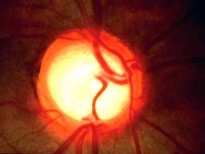

男,6岁,其家长诉患儿喜眯眼视远。视力:右0.4,左0.1,眼前后节检查未发现明显异常。其睫状肌麻痹下验光结果为:右 +5.00DS+1.00DC×90°=0.6,左 +5.00DS+1.00DC×85°=0.6,应诊断为()